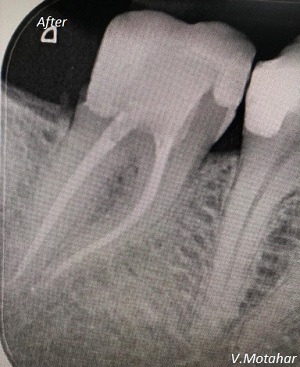

Root Canal Treatment on a molar tooth!

before

after